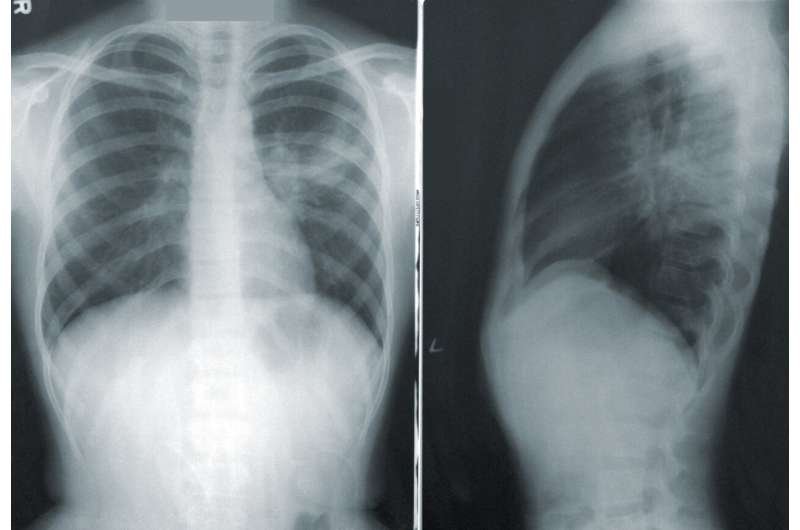

Kanceri i mushkërive është shkaku kryesor i vdekjeve nga kanceri në botë, duke shkaktuar rreth 1.8 milionë vdekje çdo vit. Shkalla e mbijetesës për ata me format e avancuara të sëmundjes, ku tumorët janë përhapur, është veçanërisht e ulët

Ekspertët tani po testojnë një vaksinë të re që udhëzon trupin për të gjetur dhe shkatërruar qelizat e kancerit, duke parandaluar rikthimin e tyre. E njohur si BNT116 dhe e prodhuar nga BioNTech, vaksina është krijuar për të trajtuar kancerin e mushkërive të qelizave jo të vogla (NSCLC), forma më e zakonshme e sëmundjes.